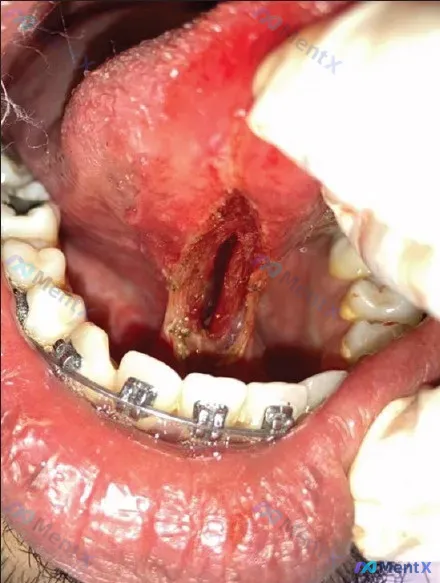

整理了一个很有警示意义的舌部创面病例,思路和常规可能不太一样,分享一下。 病例核心信息 - 关键影像描述:舌腹正中偏下可见长梭形开放性深创面,深凹状,无明显缝合痕迹;基底暗红,有黄白色渗出物,创缘充血水肿;最关键的一点——颏舌肌(genioglossus)可见。 - 局部背景:下前牙区佩戴有正畸托槽...